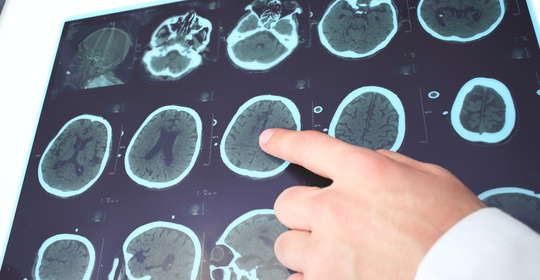

大腦與神經

感覺性失語:大腦語言功能區受損

本文介紹了運動性失語症和非流利性失語症兩種常見的言語障礙。運動性失語症是由於大腦皮層語言功能區受損導致患者無法有效地表達自己,而非流利性失語則是指患者的言語流暢度下降,詞彙檢索困難。這兩種症狀都表明了大腦對語言處理的能力受到了損害,可能與腦部受傷、中風或其他神經系統疾病有關。